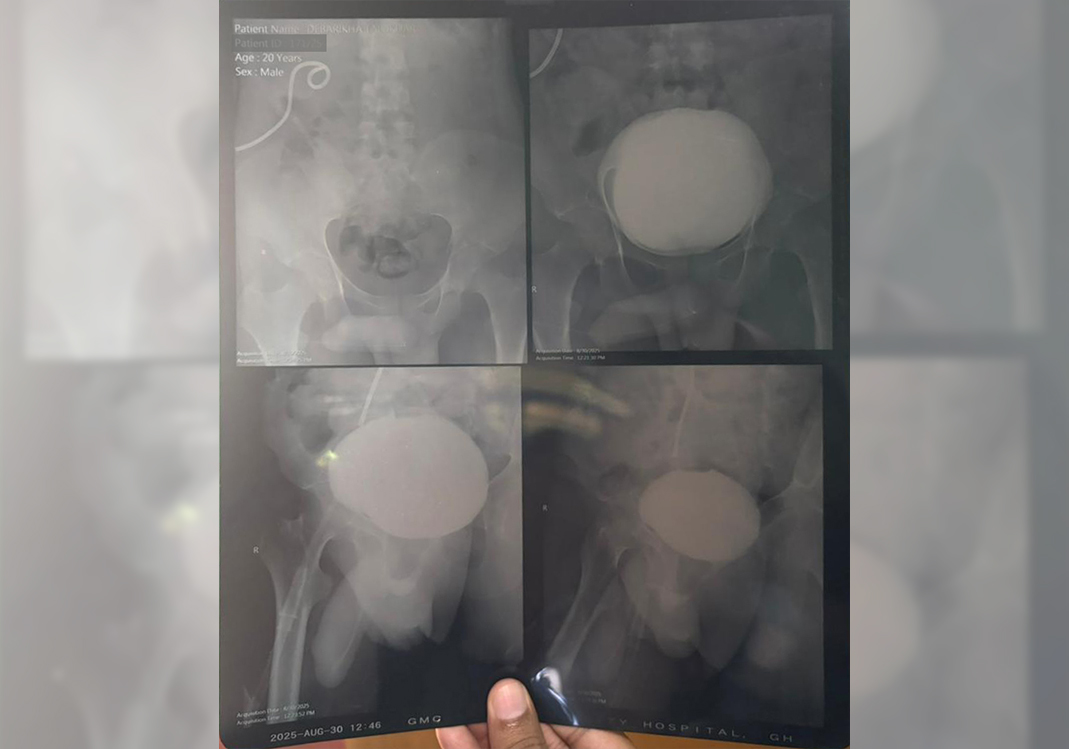

A tragic accident changed everything. A speeding tempo struck Debarshi, leaving him severely injured and fighting for his life. He was rushed to the hospital, where doctors saved him from the brink of death… but his kidneys were badly damaged.